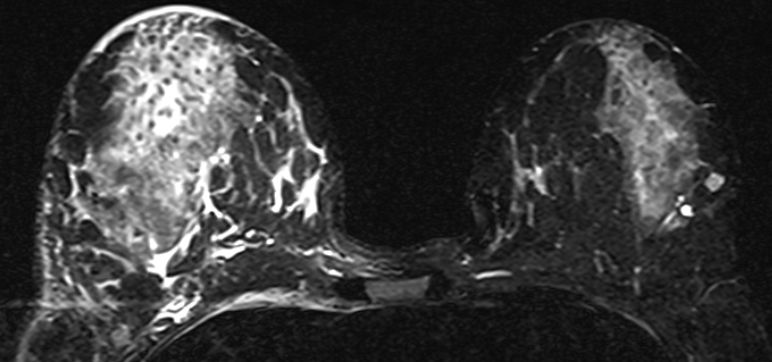

axilläre Metastasen ohne Primärtumor 51-jährige Frau mit axillärem Tastbefund. Mammographie und Sonographie o.B. Das MRT zeigt deutlich die axillären Lymphknoten.

MR im eThrive HR tra sense - Modus: Deutlich Darstellung einen 40mm großen Tumors.

Schnelle Anflutung und langsames Wash-Out sprechen für Malignität.